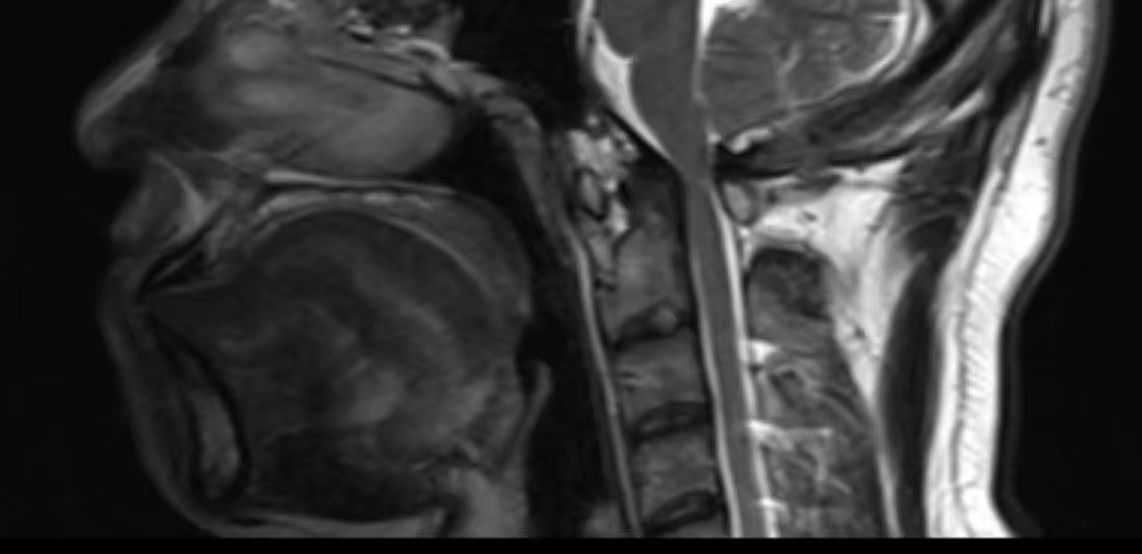

• 诊断:寰枢椎脱位

• 影像:

• 术后状况:术前患者同意不放融合器,术中切了后宫,术后复位还不错

• 术后影像: